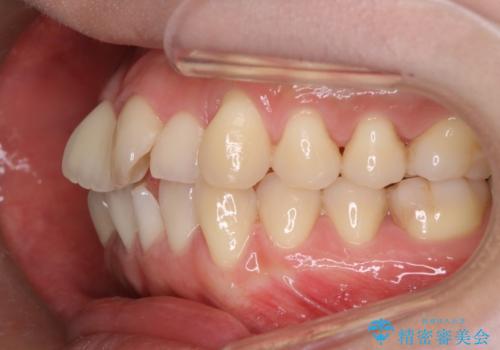

- 上の前歯のデコボコが気になるということで来院されました。

叢生量(デコボコ)が多いため、上下左右4番目の歯を抜歯してワイヤー矯正を行う治療計画を立てました。

主訴である前歯のデコボコが改善され、噛みあわせも綺麗になりました。